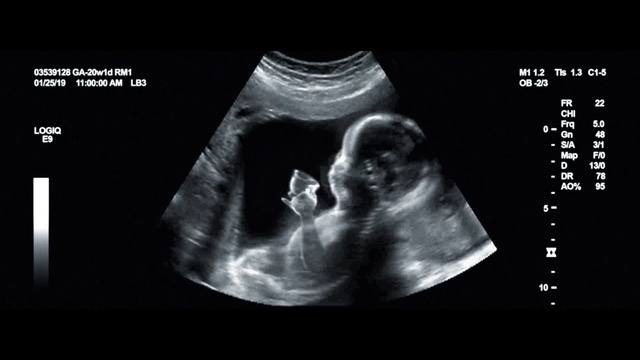

Best Video References: Infant ultrasound

Featured videos selected by a smart neural network algorithm